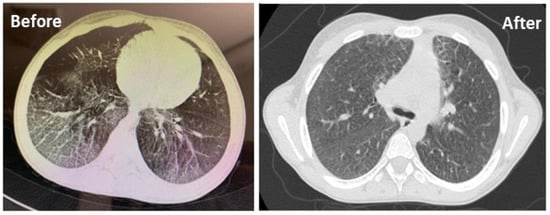

3.7. Lung HRCT